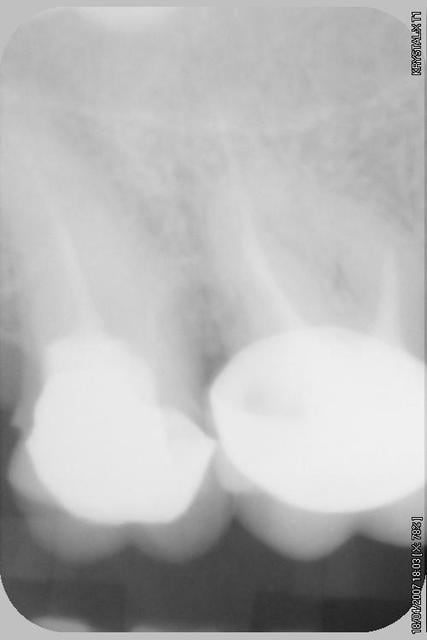

Apres quelques temps sur le fauteuil je suis parvenue a instrumenter le MV, et j'ai deouvert un faux canal sur le palatin, apres quinzes jours le signes cliniques ont disparuent.

Alors origine des douleurs? Pour moi ce n'est pas le MV mais bien le faux canal de la racine palatine, bien que la patiente se soit retrouvée chez moi a cause de la courbure du MV.

et le dv il me semble pas obturé ou trés peu sur la premier radio non?

Il y avait de la gutta dedans lors du retraitement, les trois cannaux peuvent etres a l'origine de cette douleur, c'est clair, le probleme c'est qu'en 5 ans aucuns signes radio n'est venu confirmer quoi que ce soit, et cela chez plusieurs dentistes, et je ne veux pas croire qu'ils doivent tous changer leur capteur... ;)